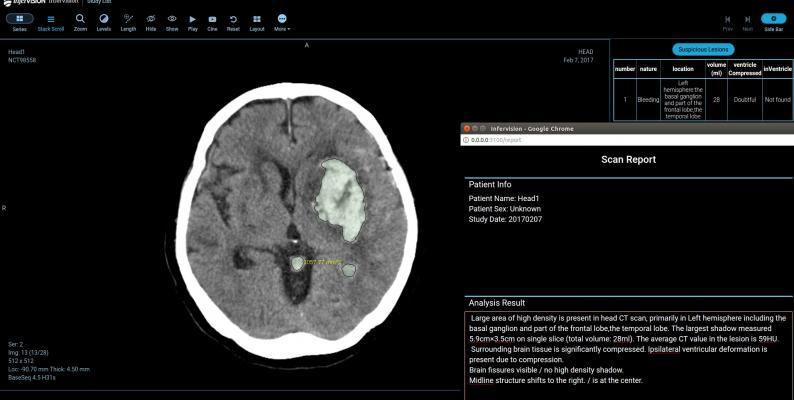

It is a condition that develops what is a stroke? A stroke is a medical condition in which poor blood flow to the brain causes cell death. It is a condition that develops what is a stroke? Ischemic, due to lack of blood flow, and hemorrhagic, due to bleeding.